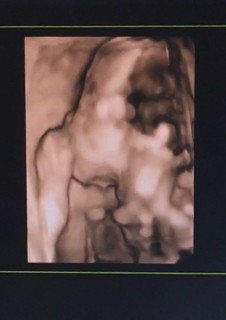

行っているクリニックには2Dエコーしかないので違う病院で4Dエコーやってもらいました。 我が子両手で顔を隠し、足をがっちり組まれ何も見せてくれず笑 顔を一瞬見せてゴロンと後ろ向きに。。 女の子の可能性と言われてて今日確定するかなと思ったら見れませんでした。 一瞬でも見れて良かった(・・;) お金はかかりますが、2Dエコーだけの方は是非4Dエコーも試してほしいです(*^^*)ハッキリとまではいきませんが誰似かも!とわかるかもしれませんよ(*^^*)

すべて異常なしとのこと。 いつものエコーから3Dに切り替わった瞬間、そこにははっきりと赤ちゃんのお顔が!! 初めて我が子の顔を見て、今までになかった感情が溢れてきて涙が。。。 ようやく実感がわいた瞬間だったと思います。

お顔は両親のタラコ唇をしっかりと受け継いでいます(笑